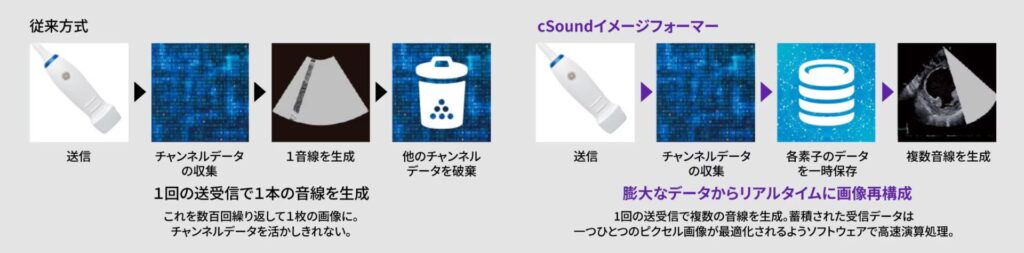

XDclear Probe

進化を遂げたプローブ技術により、深部から浅部まで高画質に描出できるようになっています。革新的な圧電体Single Crystal、音響エネルギーを有効活用するAcoustics Amplifier、温度上昇を軽減するCool stack。この3つの組み合わせにより、S/N、分解能、ペネトレーションすべてを向上しています。